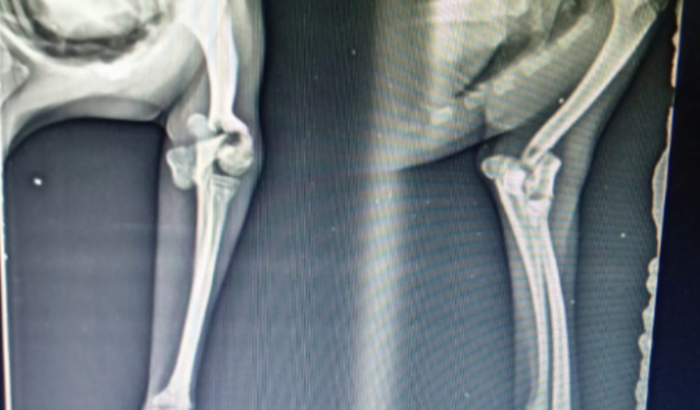

Cirurgia do Pipoca

Oi me chamo Nathalia tenho um cachorrinho e ele acabou caindo e fraturando o braçinho e precisa fazer uma cirurgia e o valor da a cirugia é 2,500 e não tenho condição de pagar esse valor Preciso de ajuda !  ver tudo

Oi me chamo Nathalia tenho um cachorrinho e ele acabou caindo e fraturando o braçinho e precisa fazer uma cirurgia e o valor da a cirugia é 2,500 e não tenho condição de pagar esse valor Preciso de ajuda !